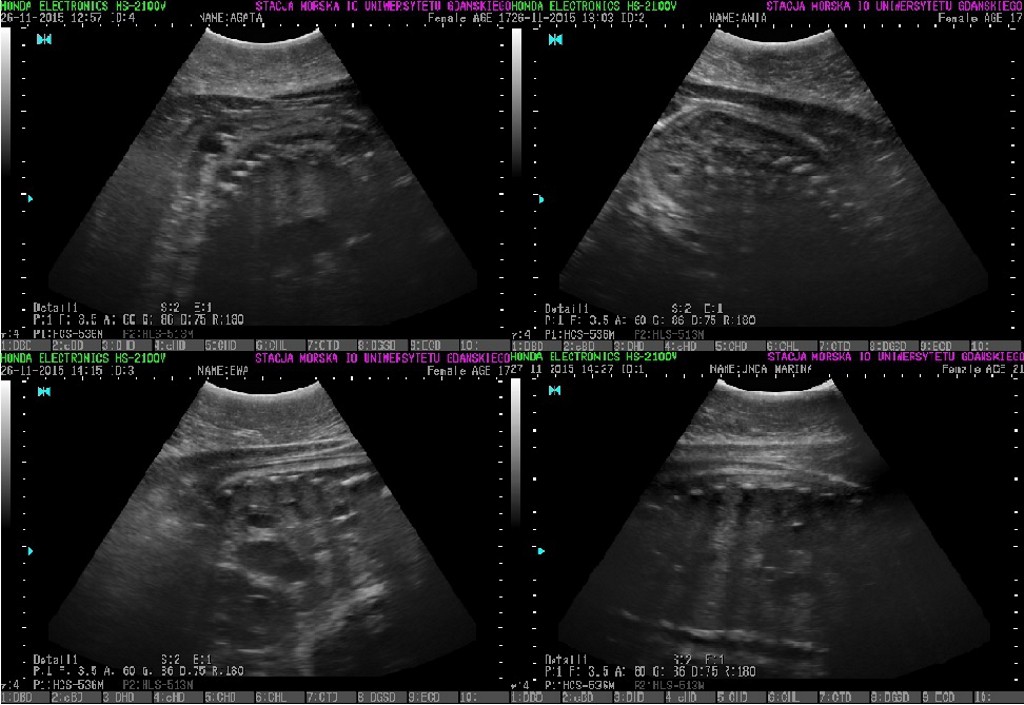

Ania, Ewa, Unda i Agata są w ciąży. Badanie USG potwierdziło, że foki spodziewają się młodych. Ssaki muszą teraz więcej jeść, żeby zgromadzić niezbędne zapasy tłuszczu, co umożliwi im nie tylko przetrwanie zimy, ale i wykarmienie potomstwa.

W związku z zaobserwowaniem zmiany apetytu opiekunowie zdecydowali o wykonaniu badania USG dla zweryfikowania, czy samice są ciężarne.

Foka Agata jest najmniej doświadczoną matką, to "dopiero" jej piąta ciąża. Pozostałe focze mamy są znacznie bardziej doświadczenie w tym zakresie. Unda rodziła 14 razy, a Ewa i Ania po 10. Z informacji Stacji Morskiej wiemy, że aktualnie szczenięta rozwijają się prawidłowo.